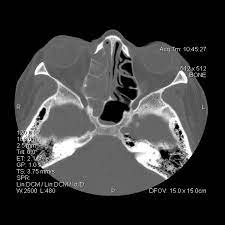

Sinusitis Nasennebenhohlenentzundung Ursachen Symptome

Sinusitis Nasennebenhohlenentzundung Ursachen Symptome from cdn.aws.klosterfrau.com